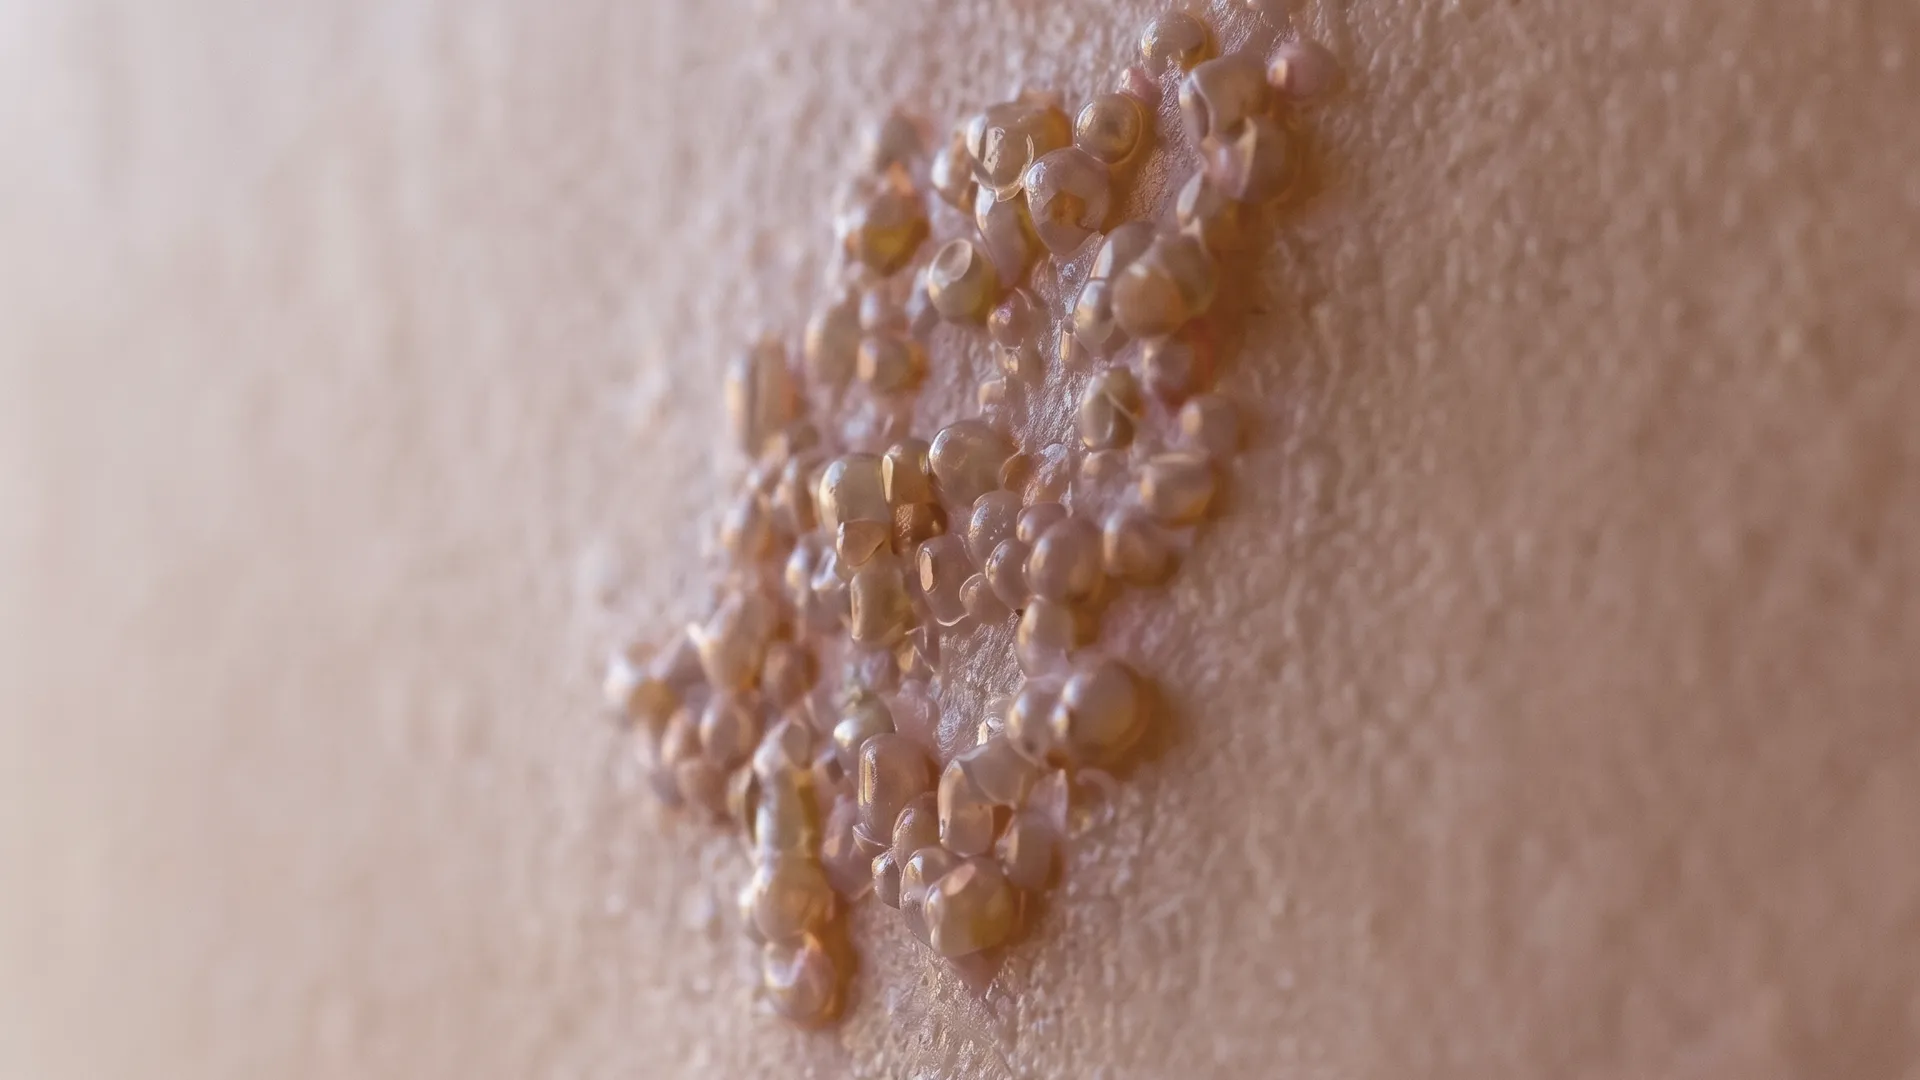

대상포진의 증상

Symptoms of Shingles

대상포진의 대표적인 증상은 피부 통증과 띠 모양 발진, 수포 발생입니다.

수포 부위에 따가움·감각 이상이 동반될 수 있습니다.

※ 대상포진은 신경을 따라 띠 모양의 발진과 수포, 통증이 나타나며, 면역 상태에 따라 증상이 달라집니다.

피부에 따끔거림·통증 후 수포 발생

한쪽 신체에 띠 모양의 발진 및 수포

수포 부위의 극심한 통증 및 감각 과민

수포 부위의 가려움·따가움

피부 병변이 딱지로 변하며 회복

심한 경우 대상포진 후 신경통(PHN) 발생

대상포진의 증상

Symptoms of Shingles

대상포진의 대표적인 증상은 피부 통증과 띠 모양 발진, 수포 발생입니다.

수포 부위에 따가움·감각 이상이 동반될 수 있습니다.

※ 대상포진은 신경을 따라 띠 모양의 발진과 수포, 통증이 나타나며, 면역 상태에 따라 증상이 달라집니다.

피부 따가움·통증 후 수포 발생

한쪽 신체에 띠 모양의 발진

수포 부위 통증 및 감각 이상

가려움·따가움 동반

수포가 딱지로 변하며 회복

대상포진 후 신경통(PHN) 발생 가능